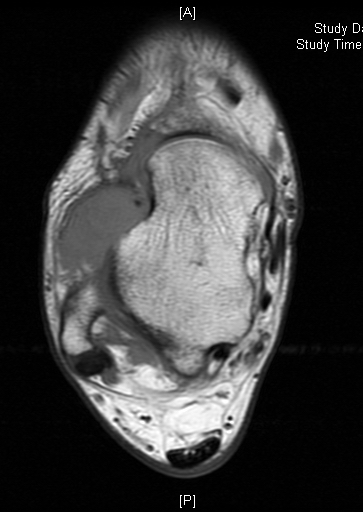

MRI

Shows multiloculated, heterogeneous mass.

“Triple Signal Intensity sign”; hypointense, isointense and hyperintense with fat on T2 – weighted MRI imaging. This sign is present in 30 to 50% of the cases. (Fig.3)

Under contrast enhancement Synovial Sarcoma appears heterogeneous and demonstrate areas of nodular enhancement.

In approximately 30% of cases a multiple vascular cannel may be identified

Synovial sarcomas may have a cystic appearance and are often mistaken for ganglion cysts especially those adjacent to tendons and in the foot and ankle.